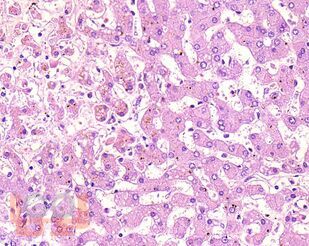

В учебном пособии представлен теоретический материал, перечень макропрепаратов и микропрепаратов, демонстрирующих типовые проявления патологических процессов. В цветных иллюстрациях и в описании микропрепаратов сделан акцент на наиболее важных гистологических изменениях, позволяющих на светооптическом уровне диагностировать и дифференцировать состояния, отклоняющиеся от нормы, в том числе с использованием различных гистологических окрасок. Пособие помогает выделить главные аспекты изучаемых патологических процессов, организовать и конкретизировать учебный процесс.